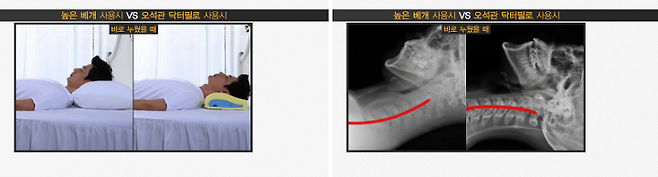

오 대표와 오 원장은 여러 가지 생활습관 중 수면 중 자세를 살폈다. 많은 이들이 부적절한 베개 때문에 잠을 자는 자세가 뒤틀리고 경추에 무리를 준다는 점에 주목했다. 2006년 11월 이들은 시중에 나온 베개를 뜯어보며 바른 자세를 유지하면서도 편한 베개 개발에 착수했다.

개발은 신경외과 전문의인 오 원장이 주도했다. 오 원장은 평소 세상에서 가장 편하고 완벽한 베개는 엄마의 팔베개라는 지론을 갖고 있었다. 엄마의 팔베개는 뼈와 이를 둘러싼 근육층, 그 위의 지방층 등 삼중 구조로 이뤄졌다. 당시만 해도 기능성 베개가 흔치 않았다. 오 원장은 삼중 구조를 가진 세상에 없던 제품을 만들자는 계획에 따라 스펀지, 목제, 메모리폼, 라텍스 등으로 각종 실험을 하며 베개를 개발했다.

오 대표는 “우리 제품을 쓰고 허리나 목디스크가 호전됐다는 고객을 보면 보람을 느낀다”며 “여행을 갈 때도 드로브로스의 베개를 반드시 가지고 간다는 사람도 많다”고 했다. 그는 상품에 자신감을 비췄다. “사람이 누웠을 때의 척추 각도와 높이 등을 고려해 20년 이상의 임상 경험을 바탕으로 개발한 제품들입니다. 우리 것이 세상에서 가장 발전한 개념의 상품이라고 자신합니다.”